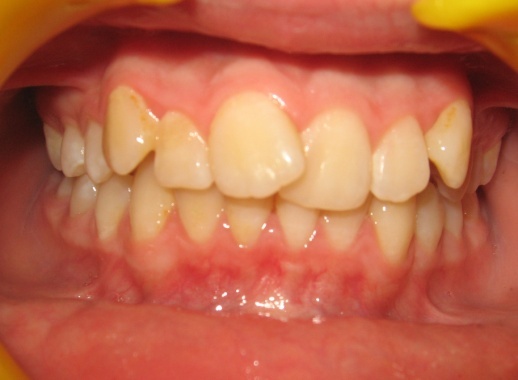

1 - Arcades dentaires avant-après

Les photos montrent un encombrement dentaire important associé à une classe II dentaire. Les extractions de prémolaires ont été décidées non seulement pour créer la place nécessaire à l’alignement, mais aussi pour corriger le décalage de classe II. Le résultat final illustre qu’un plan de traitement bien réfléchi peut répondre simultanément aux impératifs fonctionnels et esthétiques, sans compromettre l’harmonie faciale.